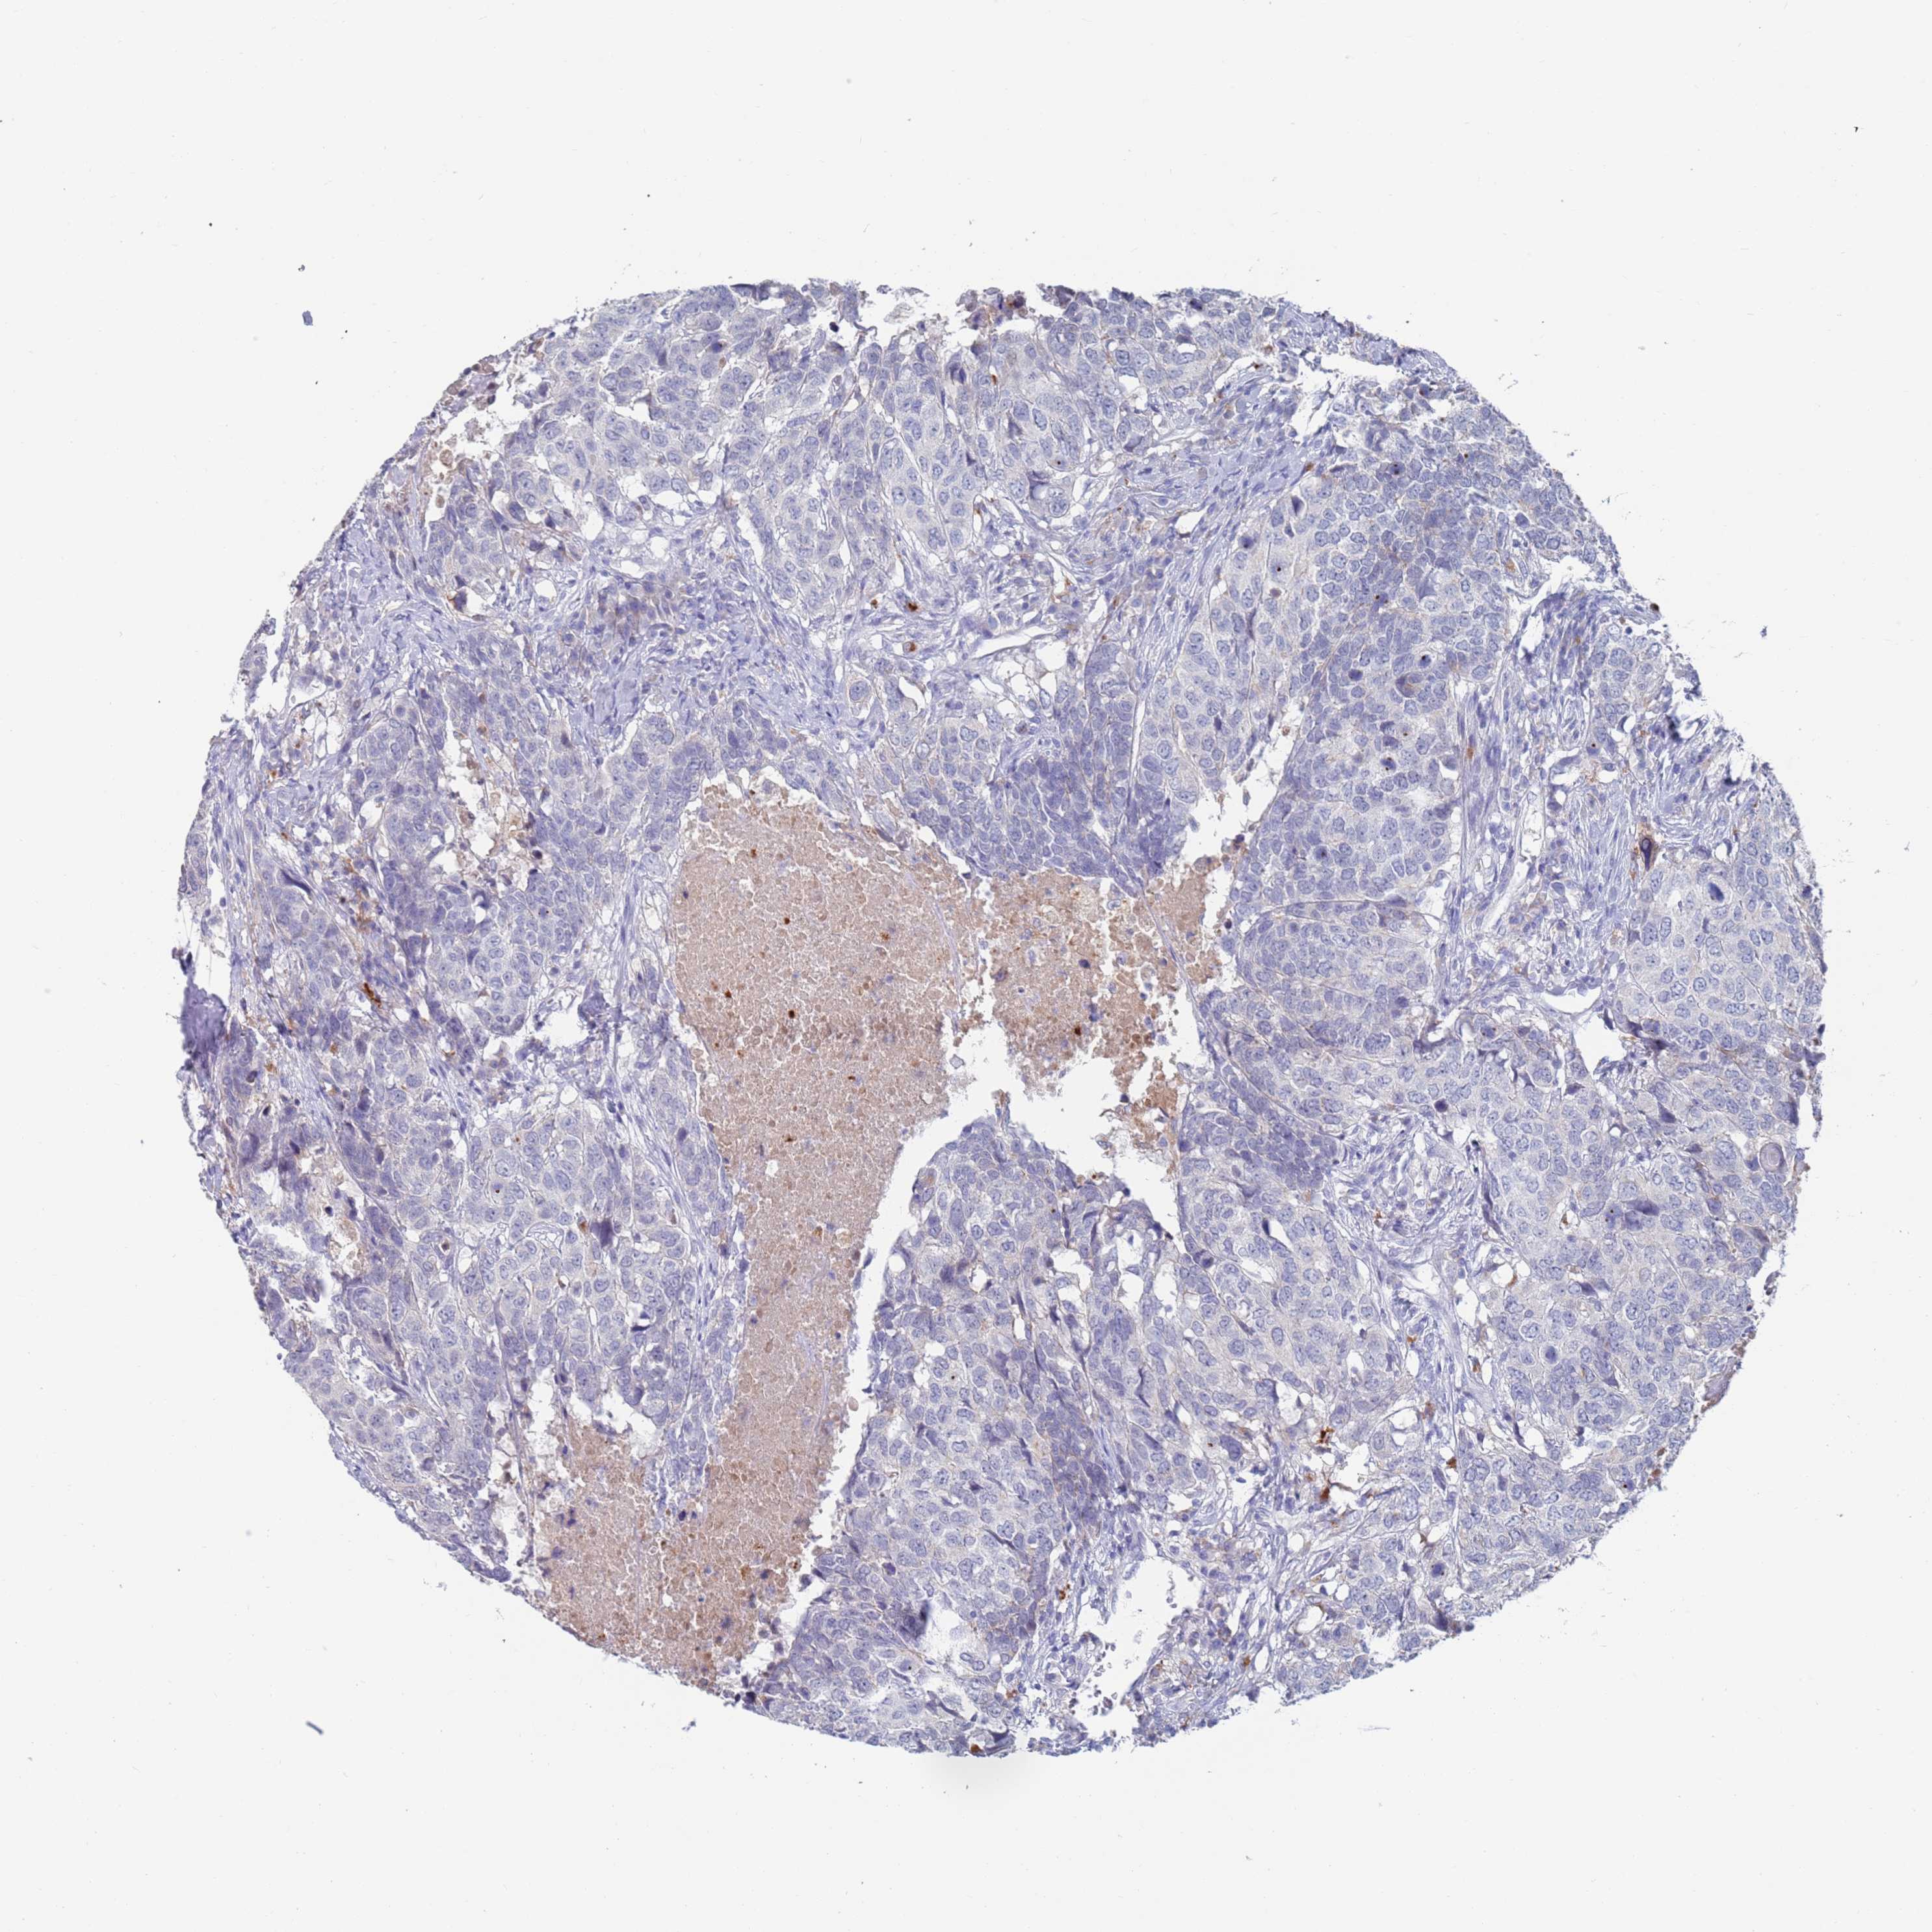

HEAD AND NECK CANCER - Protein expressioni

A mouse-over function shows sample information and annotation data. Click on an image to view it in a full screen mode. Samples can be filtered based on level of antibody staining by selecting one or several of the following categories: high, medium, low and not detected. The assay and annotation is described here.

Antibody stainingi

Antibody staining in the annotated cell types in the current human tissue is reported as not detected, low, medium, or high, based on conventional immunohistochemistry profiling in selected tissues. This score is based on the combination of the staining intensity and fraction of stained cells.

Each image is clickable and will lead to virtual microscopy that enables deeper exploration of all samples and also displays staining intensity scores, fraction scores and subcellular localization as well as patient and tissue information for each sample.

Antibody HPA056371

Staining

High

Medium

Low

Not detected

Intensity

Strong

Moderate

Weak

Negative

Quantity

>75%

75%-25%

<25%

None

Location

Nuclear

Cytoplasmic/membranous

Cytoplasmic/membranous,nuclear

Squamous cell carcinoma, NOS